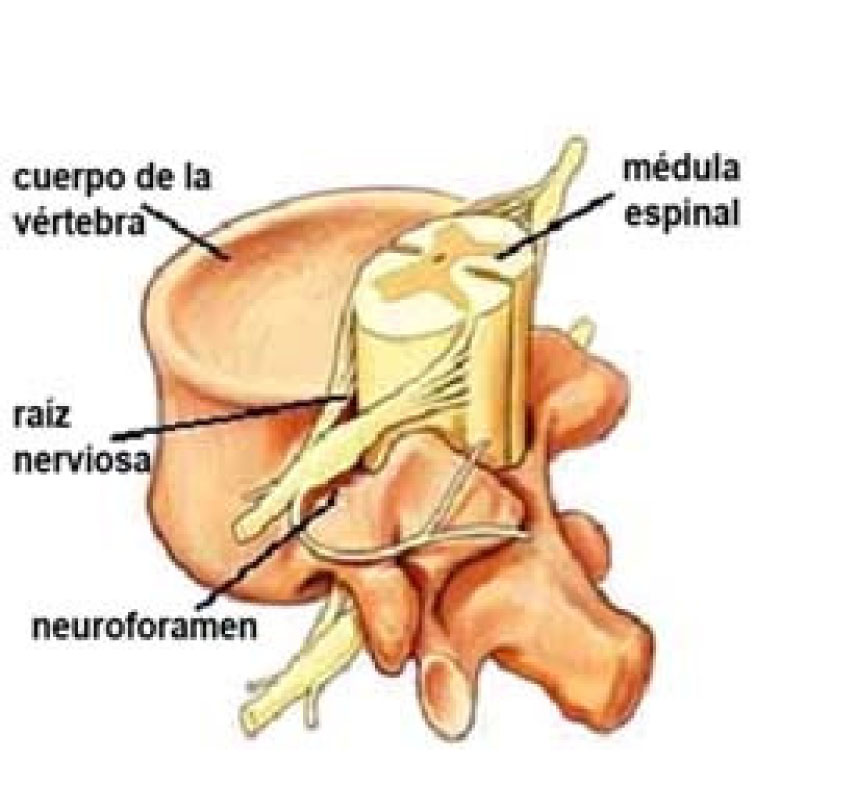

Los huesos (vértebras) de la columna protegen los nervios que salen del cerebro y bajan por la espalda para formar la médula espinal. Las raíces nerviosas son nervios grandes que se desprenden de la médula espinal y salen de la columna entre cada vértebra. (Fig 1)